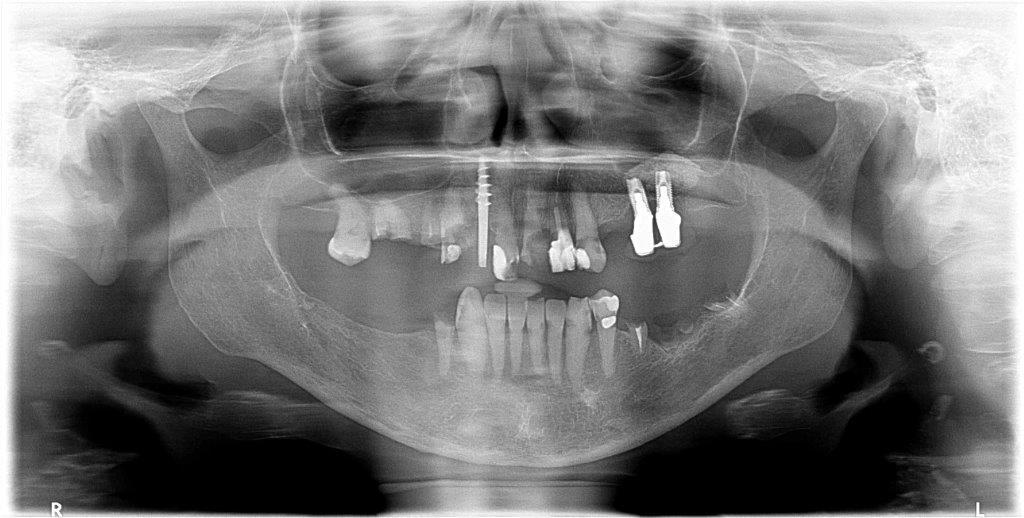

Per mostrarti che questo non è un caso limite di uno studio singolo ti mostro la panoramica di una visita delle 16 dello stesso giorno.

Questa signora, affetta da sarcoidosi per cui da anni assume glucocorticoidi (Deflan) e da epatite C per cui sta eseguendo una terapia con sofosbuvir e ribavirina si ripresenta in lacrime per la sua condizione. Il dentista continua a fargli lavori nel settore frontale che non tengono. Il 21 si è distrutto per metà e lei non esce più da giorni per questo (i pazienti a volte sono strani, lo sappiamo…in questa bocca il 21 mezzo rotto era l’ultimo dei problemi…). La signora mi dice che il dentista ha provato a trattare il 13 ma le ha detto che “non riusciva a trovare il canale perché c’è dell’osso, non ho capito bene…” E ha appuntamento per vedere che si può fare sul 13 tra una settimana, perché è andata da una catena odontoiatrica che ad agosto sarà aperta (almeno questo! ?). E nel frattempo mi chiede se il 22 va bene perché gliel’ha fatto l’ultima volta!

Evito i commenti sul tentativo di recuperare i denti volta per volta in questo caso.

Se anche la paziente non avesse i soldi per togliere tutto e affrontare una riabilitazione fissa su impianti non si può di sicuro invocare l’etica e la compassione nel tamponare una situazione del genere! Piuttosto di spillare qualche centinaio di euro ogni volta su terapie che poi non si possono garantire al paziente togli tutto e fai una dentiera! Stop! Non ci sono altri piani di cura qui!

La bonifica completa nell’arcata superiore in questo caso dovrebbe essere il primo passo comune di un piano di cura per tutti i dentisti, a meno che non si vogliano salvare per qualche astrusa teoria di “voler conservare” il 17, l’11 e gli impianti in perimplantite per tentare di ancorare una protesi parziale, ma non ha alcun senso, a parer mio.